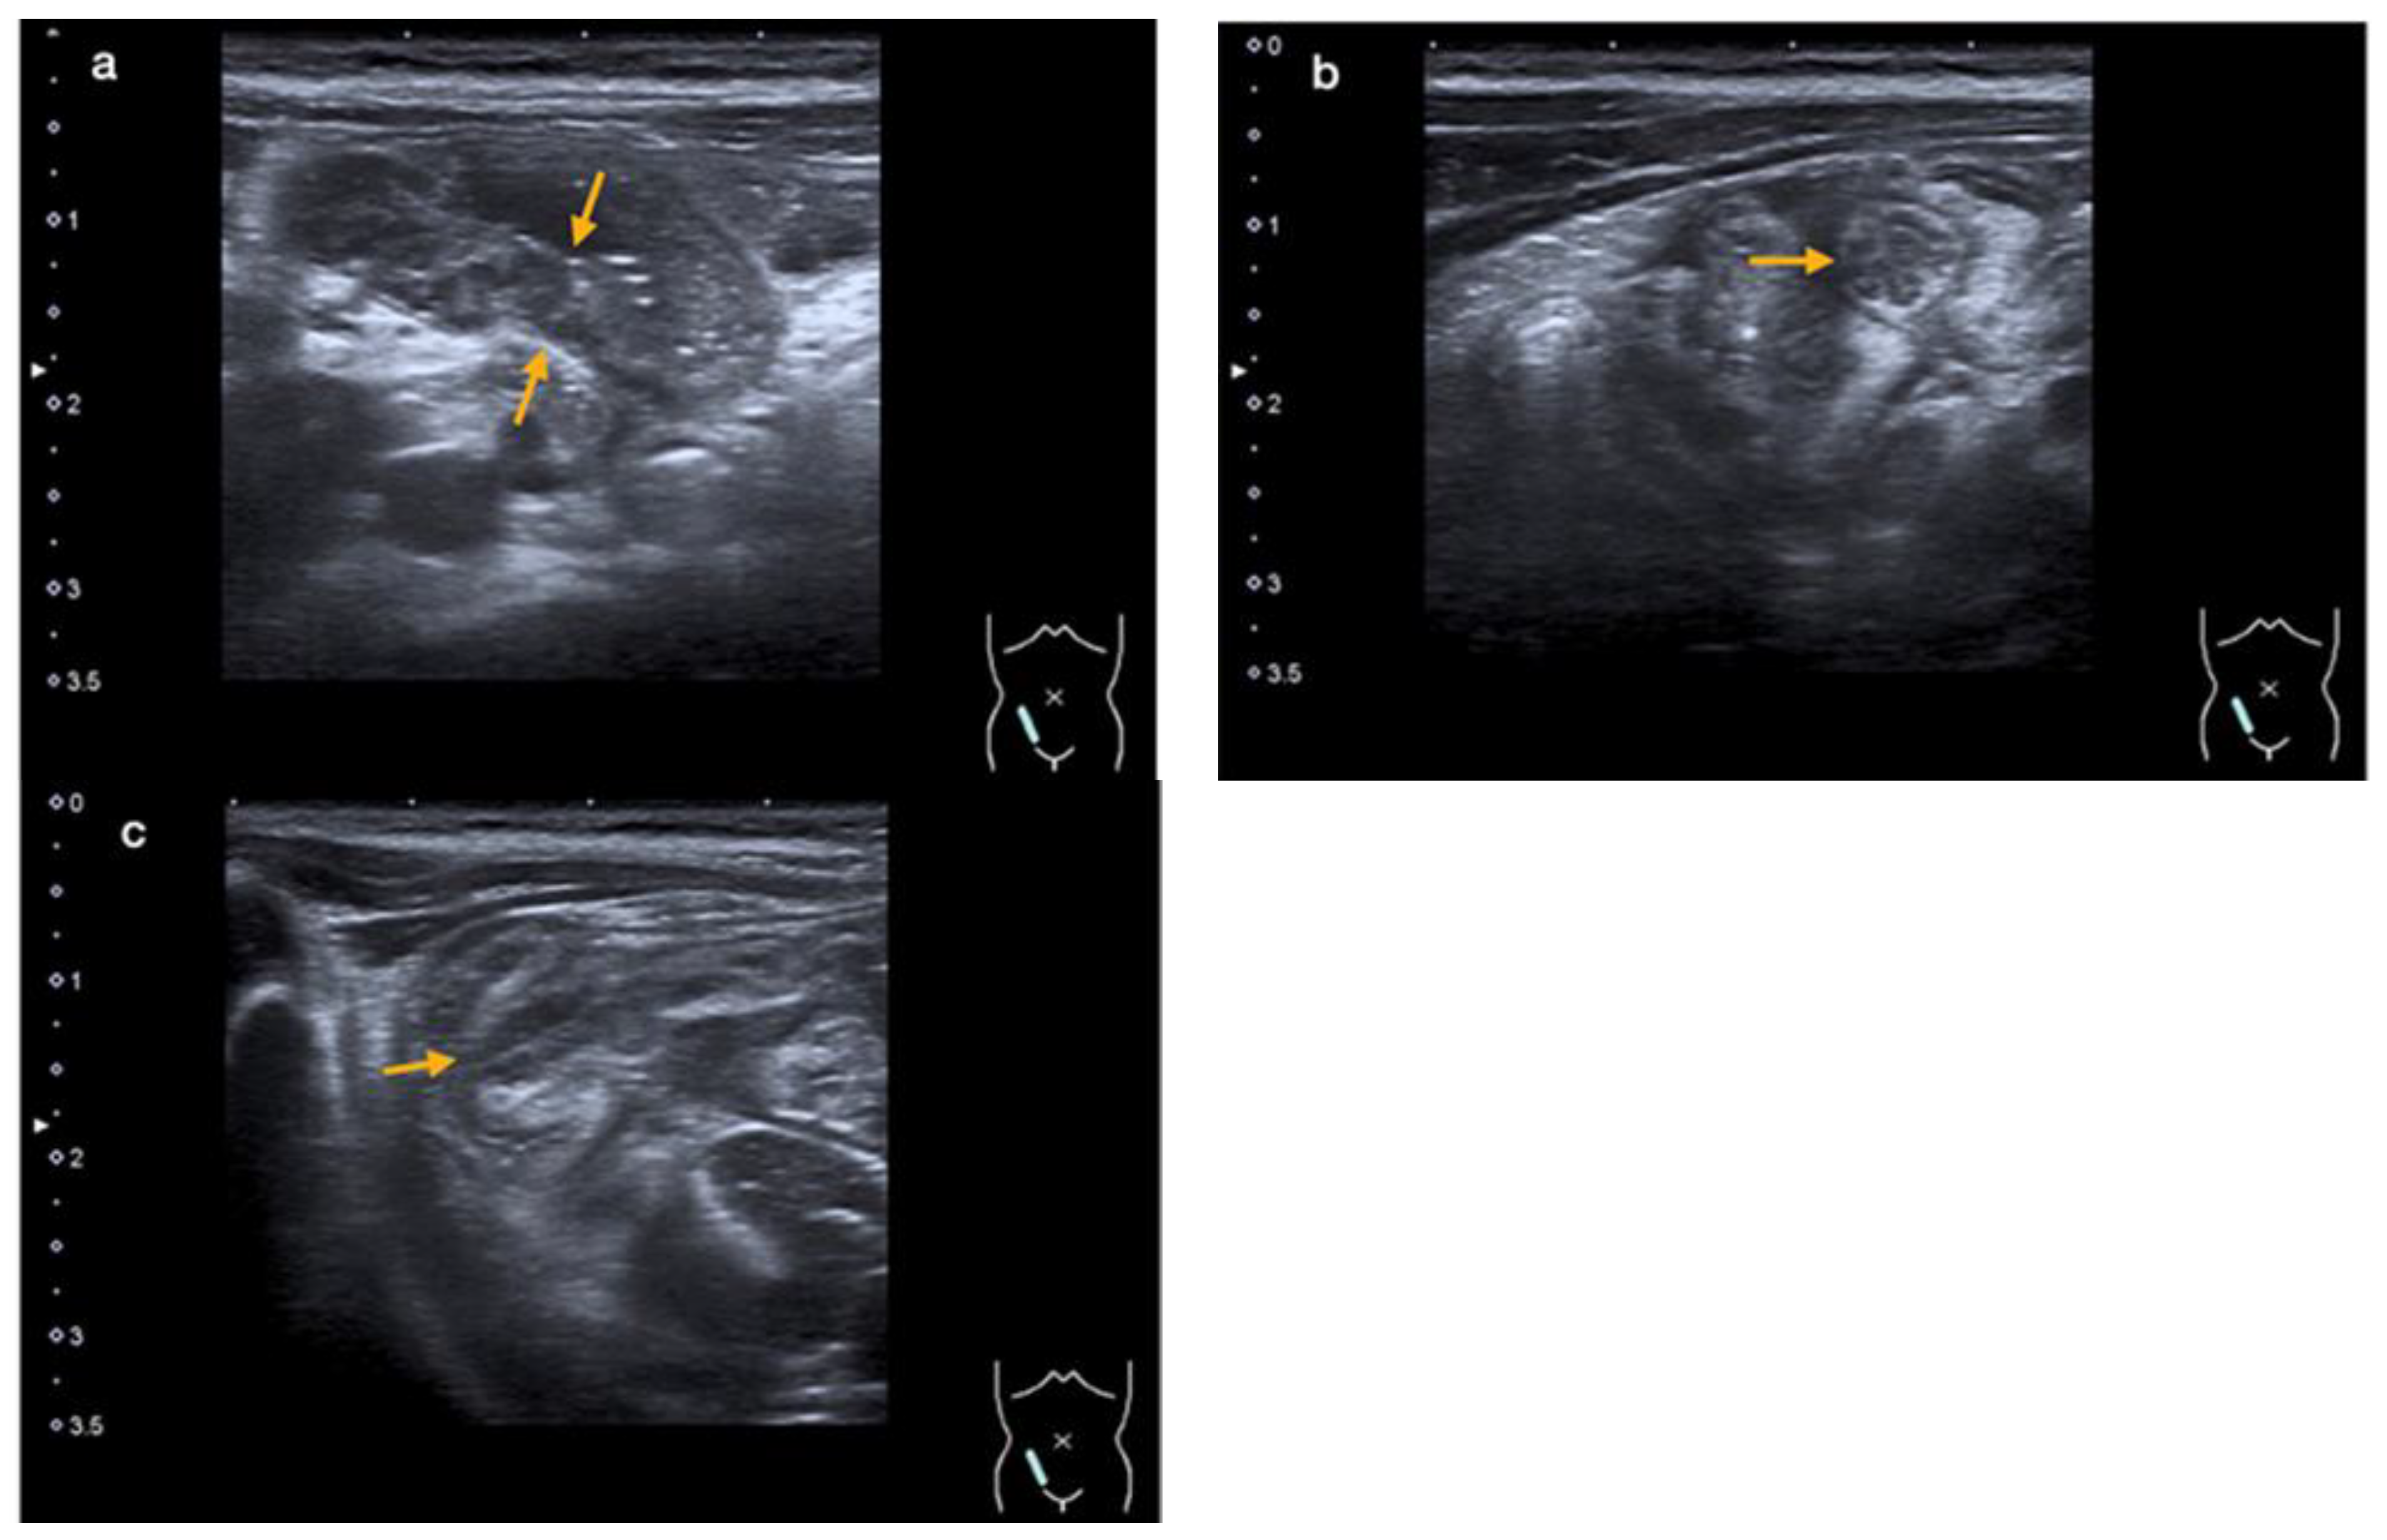

An abdominal ultrasound revealed an enteritic pattern with fluid-filled bowel loops. The bowel wall of the cecum was significantly thickened to 5 mm, along with swelling of the ileocecal valve and the wall of the terminal ileum, indicative of terminal ileitis and cecitis (Figure 2a–c).

Figure 2.

An abdominal ultrasound showing thickening of the intestinal wall of the terminal ileum (orange arrows in (a)) and the ileocecal valve (orange arrow in (b)—cross-section, and (c)—longitudinal section) (case 2).